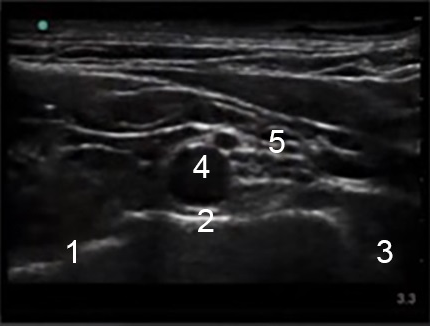

Supraclavicular Ultrasound Labeled 1 Image

Pleura

First Rib

Subclavian Artery

Brachial Plexus